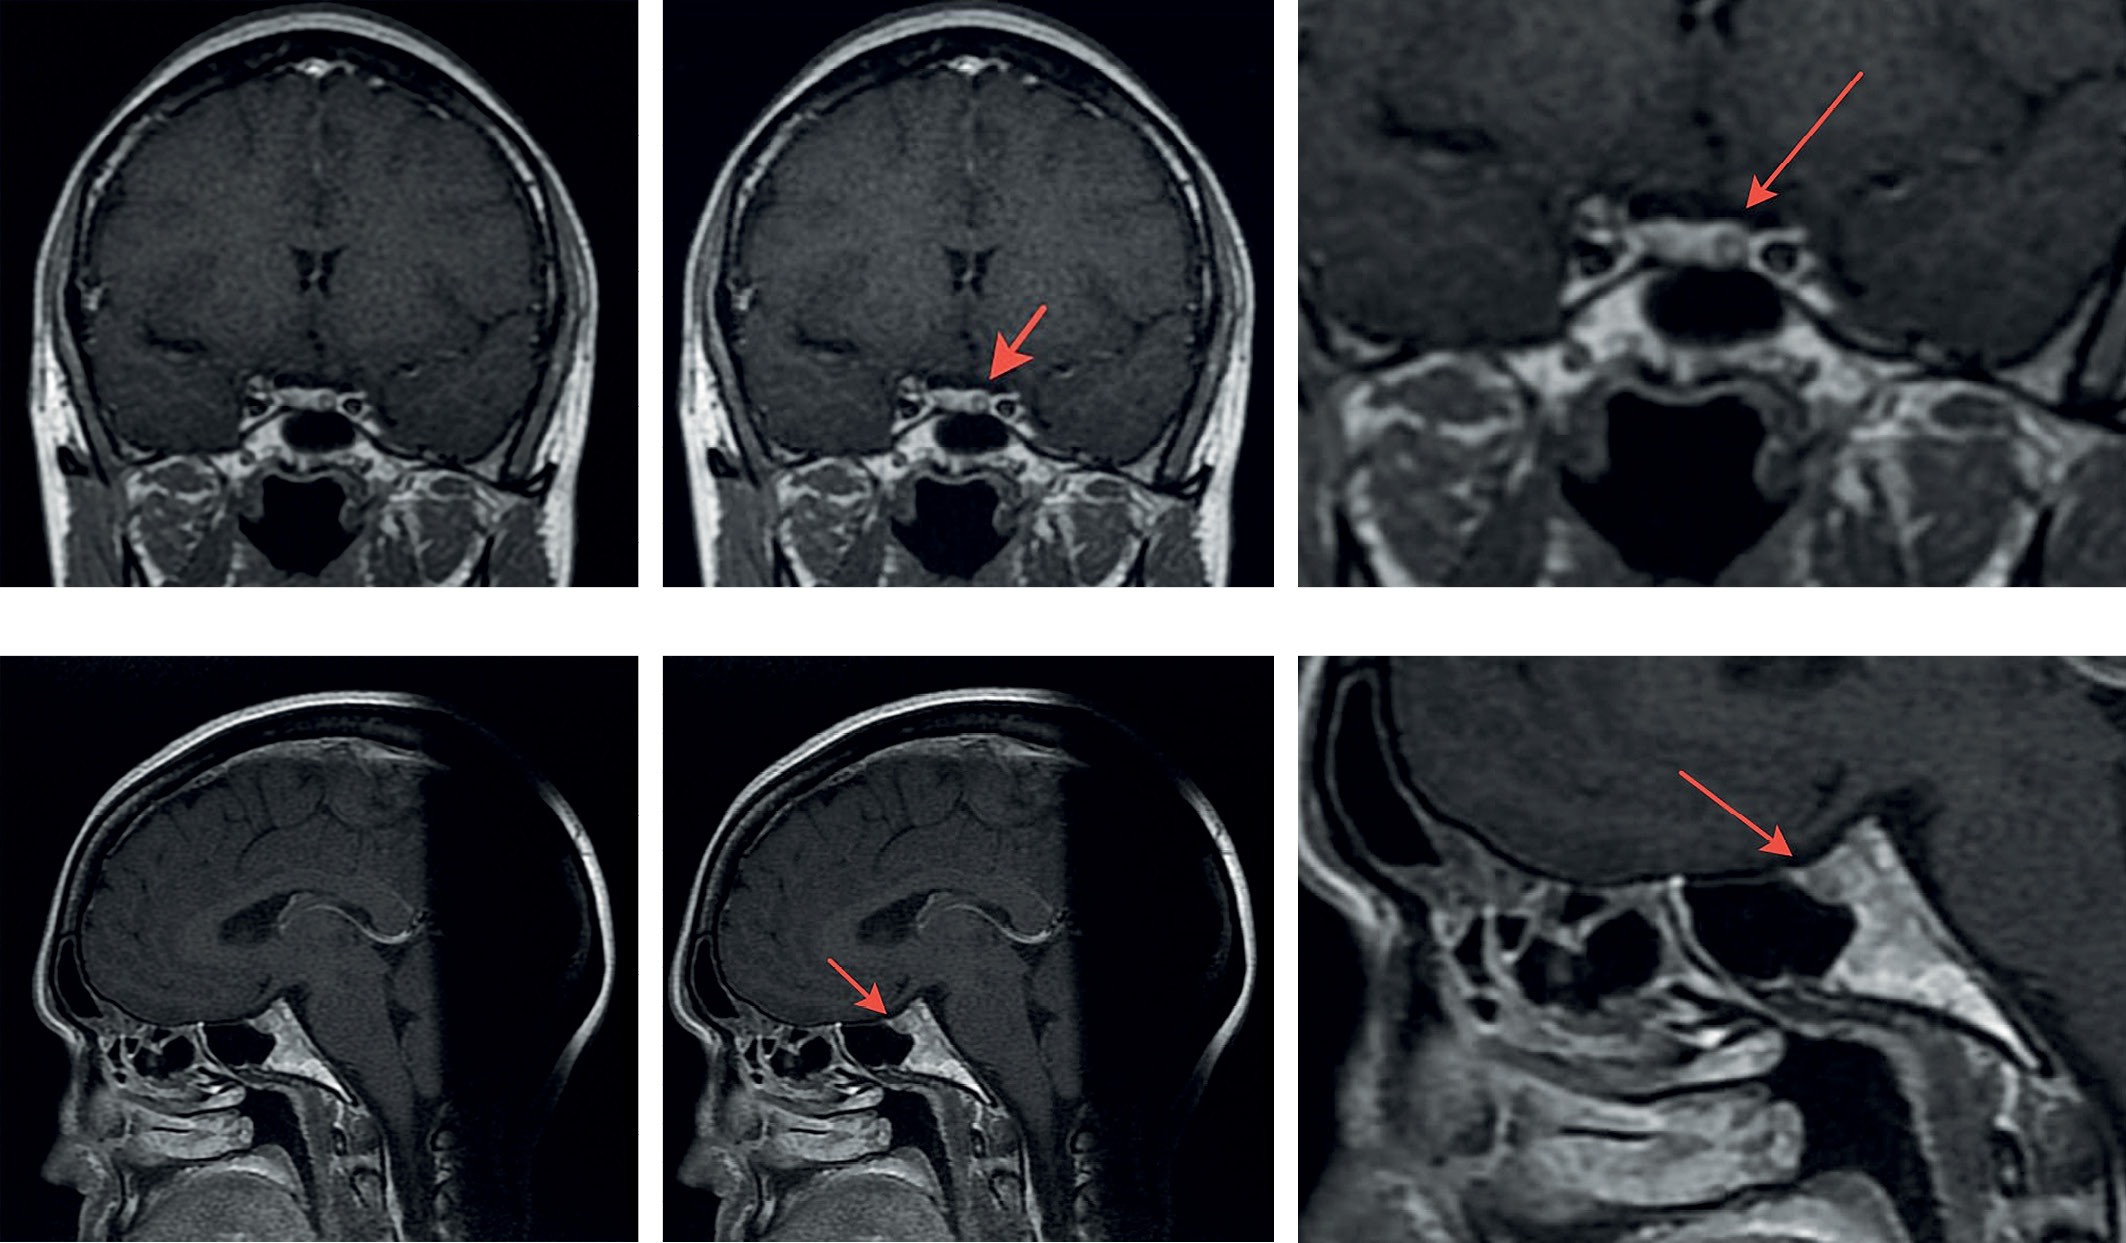

Больной рекомендована МРТ гипофиза с внутривенным контрастным усилением. Результат МPT головного мозга с внутривенным контрастным усилением (15,0 омнискан): на серии томограмм получены изображения суб- и супратенториальных структур головного мозга. В режимах T1W, T2 FLAIR и T2W патологических МР-сигналов от вещества мозга не получено. Признаков объемного образования не выявлено. Срединные структуры симметричны, не смещены. Базальные цистерны обычной конфигурации, не расширены. После внутривенного усиления гипофиз неоднородно выполнен контрастом, в левой половине гипофиза определяется микроаденома размером 4 мм в диаметре. Ножка гипофиза не отклонена. Заключение: Микроаденома гипофиза (рис. 1).

Рисунок 1. Магнитно-резонансная томография хиазмально-селлярной области. Выделена микроаденома гипофиза.

MPT головного мозга с внутривенным усилением (15,0 омнискан): на серии томограмм получены изображения суб- и супратенториальных структур головного мозга. Состояние после оперативного лечения (удаления микроаденомы гипофиза). После внутривенного усиления гипофиз однородно гомогенно накапливает контрастное вещество. Ножка гипофиза не отклонена. В режимах TIW, T2 FLAIR и T2W патологических МP-сигналов от вещества мозга не получено. Признаков объемного образования не выявлено. Заключение: органических изменений головного мозга не выявлено.